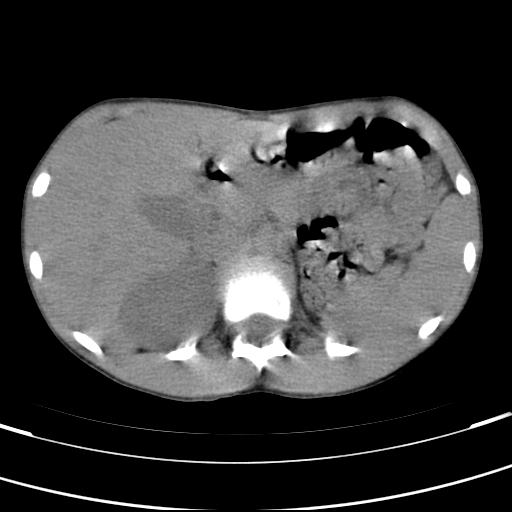

标题: PED3157:左肾缺如,请教脾脏的改变?、、

男孩,9岁。胃部不适。

脾脏位于左侧,但数个脾脏呈分离状态,左肾缺如,右肾代偿肥大。考虑多脾综合征。